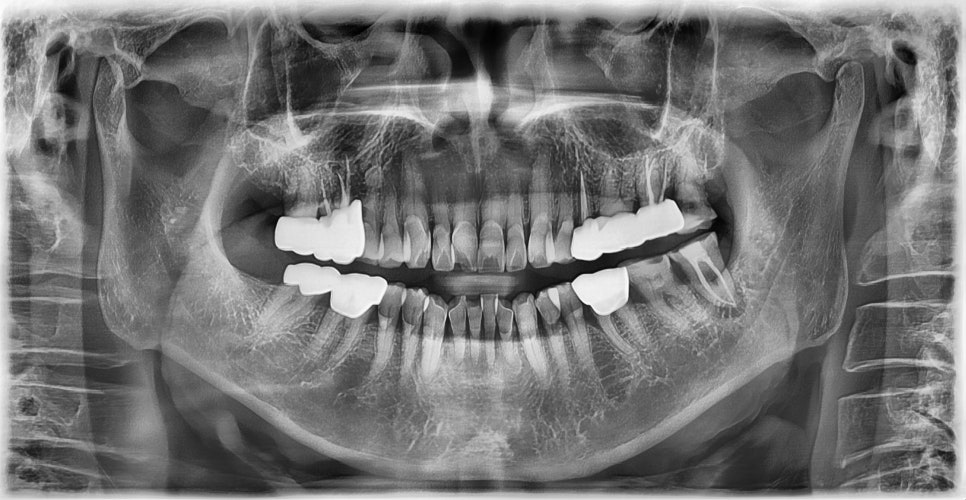

초진 X-ray (2025-1-23)

본 환자는 76세 남환으로 오른쪽 아래 어금니가 불편하여 내원하셨습니다. 문진시 당뇨병 병력이 있으셨으나, 평소 당화혈색소(HbA1c)가 6.5%로 비교적 잘 조절되고 있는 상태였습니다. 오른쪽 아래 어금니의 치근 파절로 진단되어 발치하기로 하였습니다. 마취 후 스트레스 또는 긴장으로 인하여 일시적으로 혈당이 급상승하였으나 10분 단위로 모니터링 하면서 200 이하로 혈당이 안정되는 것을 확인한 후 발치 시행하였습니다.